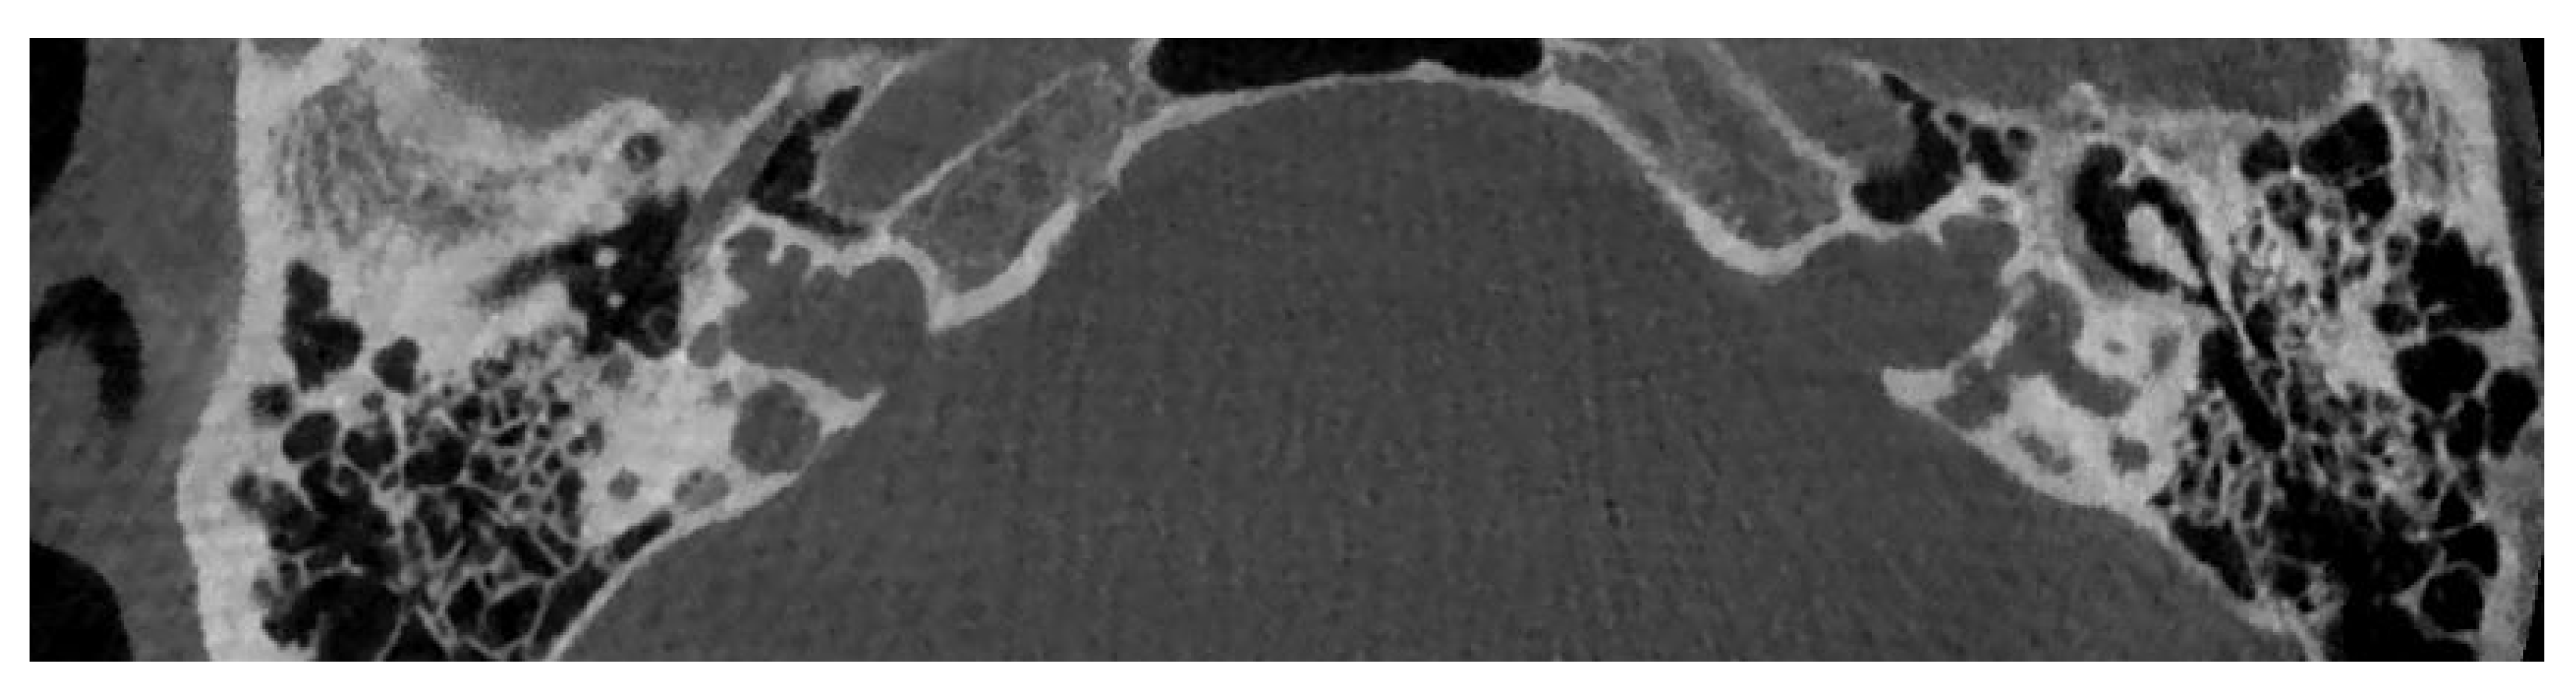

4. Common Cavity

| Common cavity deformity | Common cavity | No subgroups | Single, round chamber, representing cochlea and vestibule without any differentiation between them |